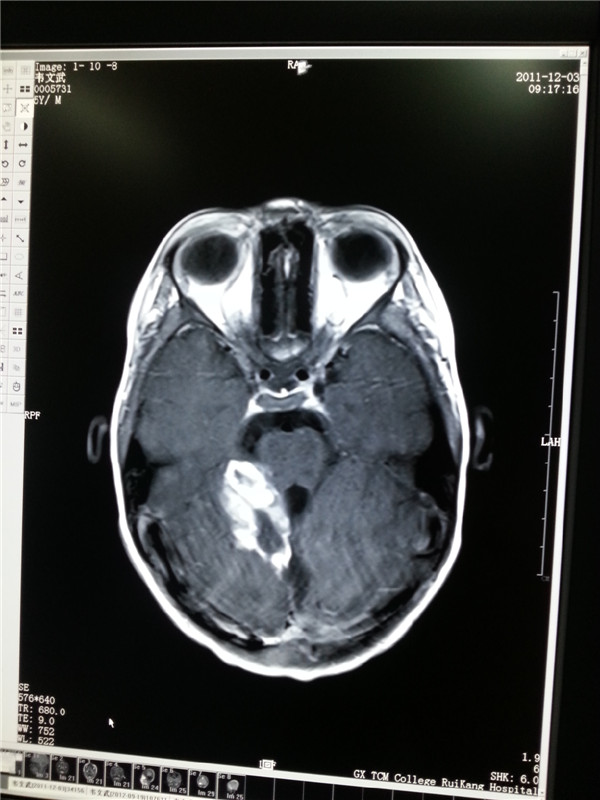

脑干长肿瘤不能开刀?射波刀一解难题

41岁的黄先生在平南县从事农贸生意,家中儿女双全,本过着幸福的生活。然而两个月前黄先生莫名出现头晕,左耳耳鸣的情形,以为是小毛病就不太...